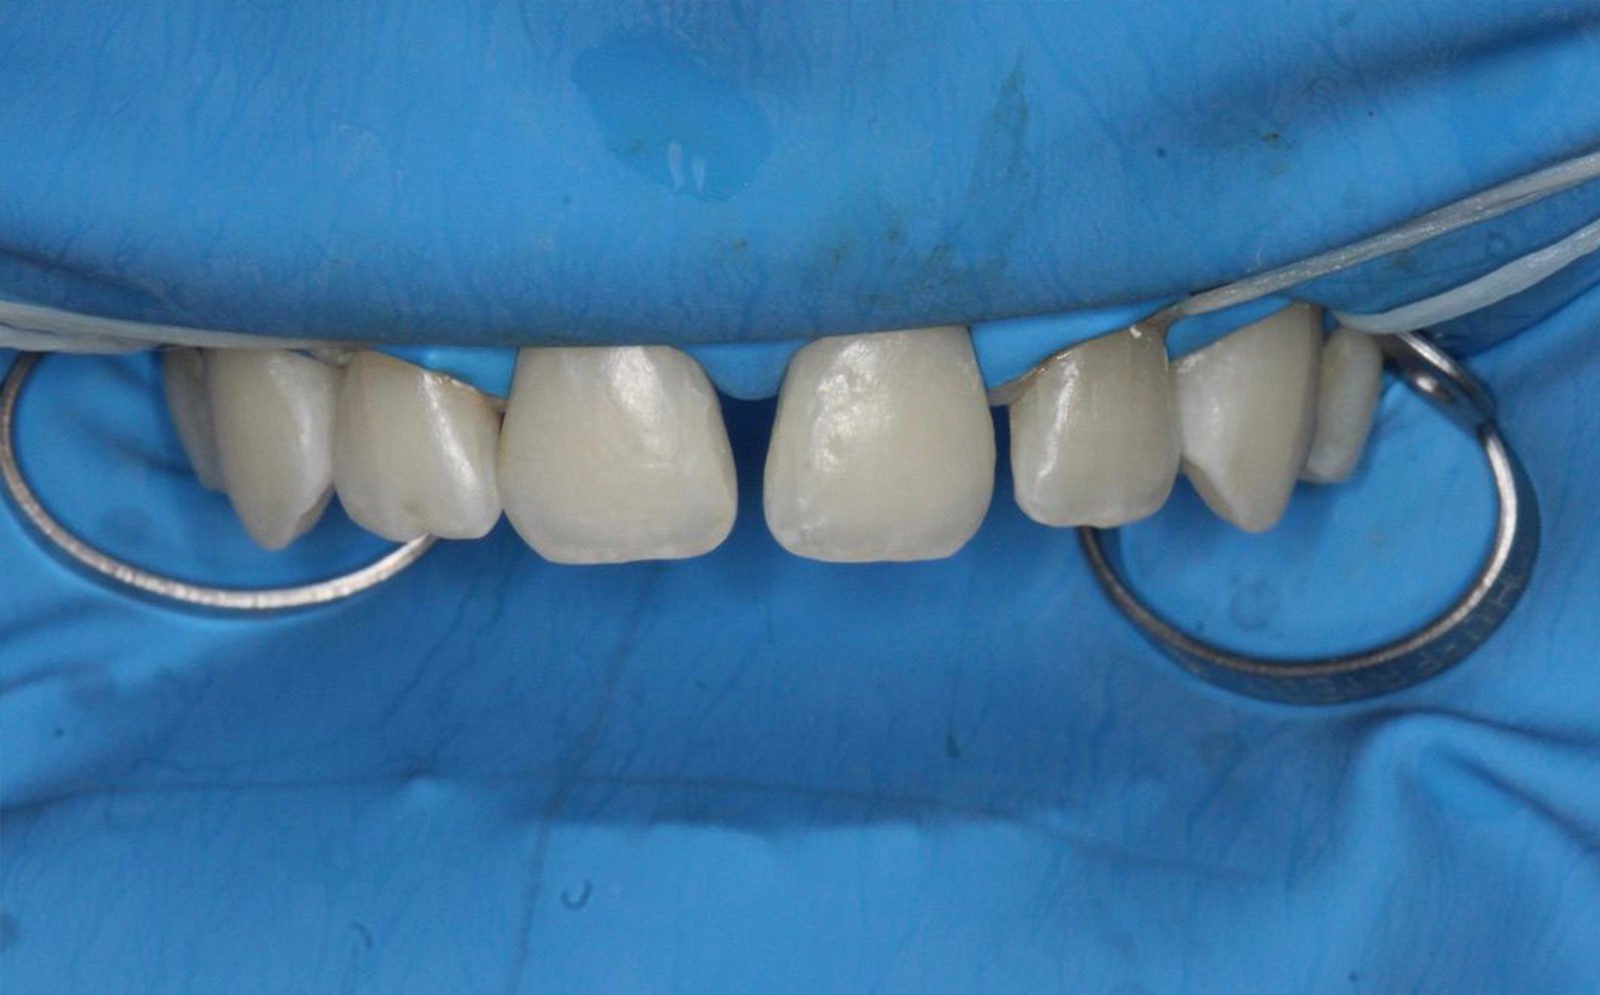

Antes

Procedimiento

Después